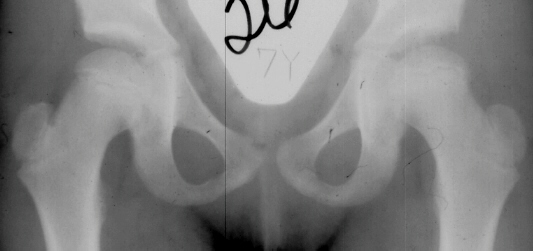

The progression of the hip is documented by x-rays taken at 1 year of age, 2 years of age, 3 years of

age, 5 years of age, 7 years of age, then at ten years of age, early closure of the lateral portion of proximal growth plate observed. Coxa valga was also observed.